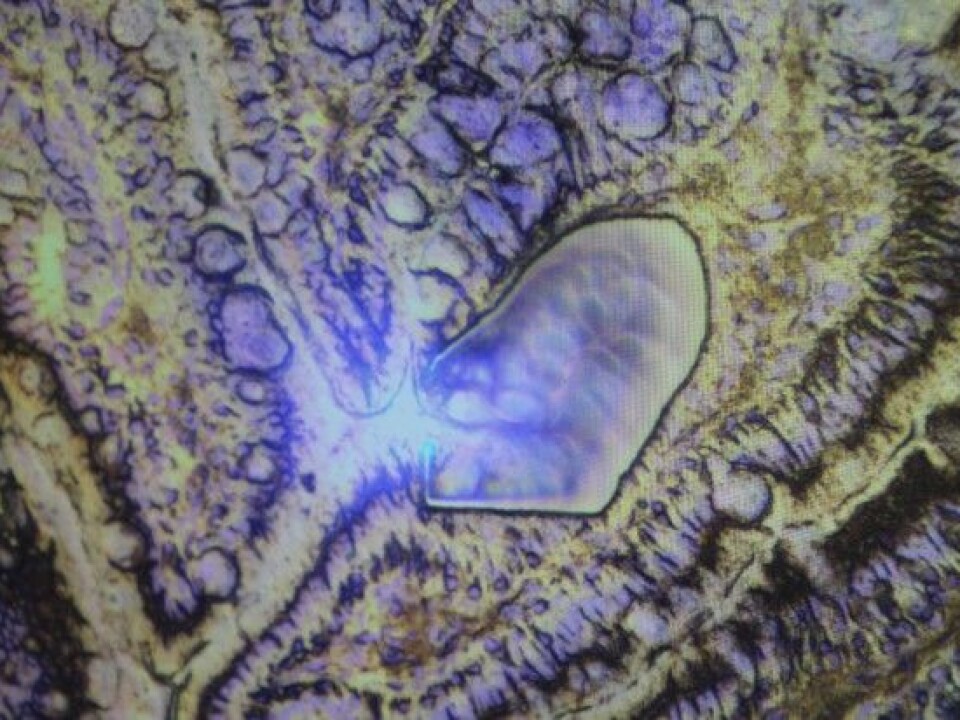

The various processes taking place in the intestine of an animal are extremely complex. What appears when you look at the animal gut as a whole may look quite different when peering through the microscope. In the laboratory, researchers are digging into the tiny details of defense cells, microorganisms, DNA and gene expressions in specific areas of the bowel.

This image actually shows part of a pig's intestine. (Photo: Liv R. Bjergene)